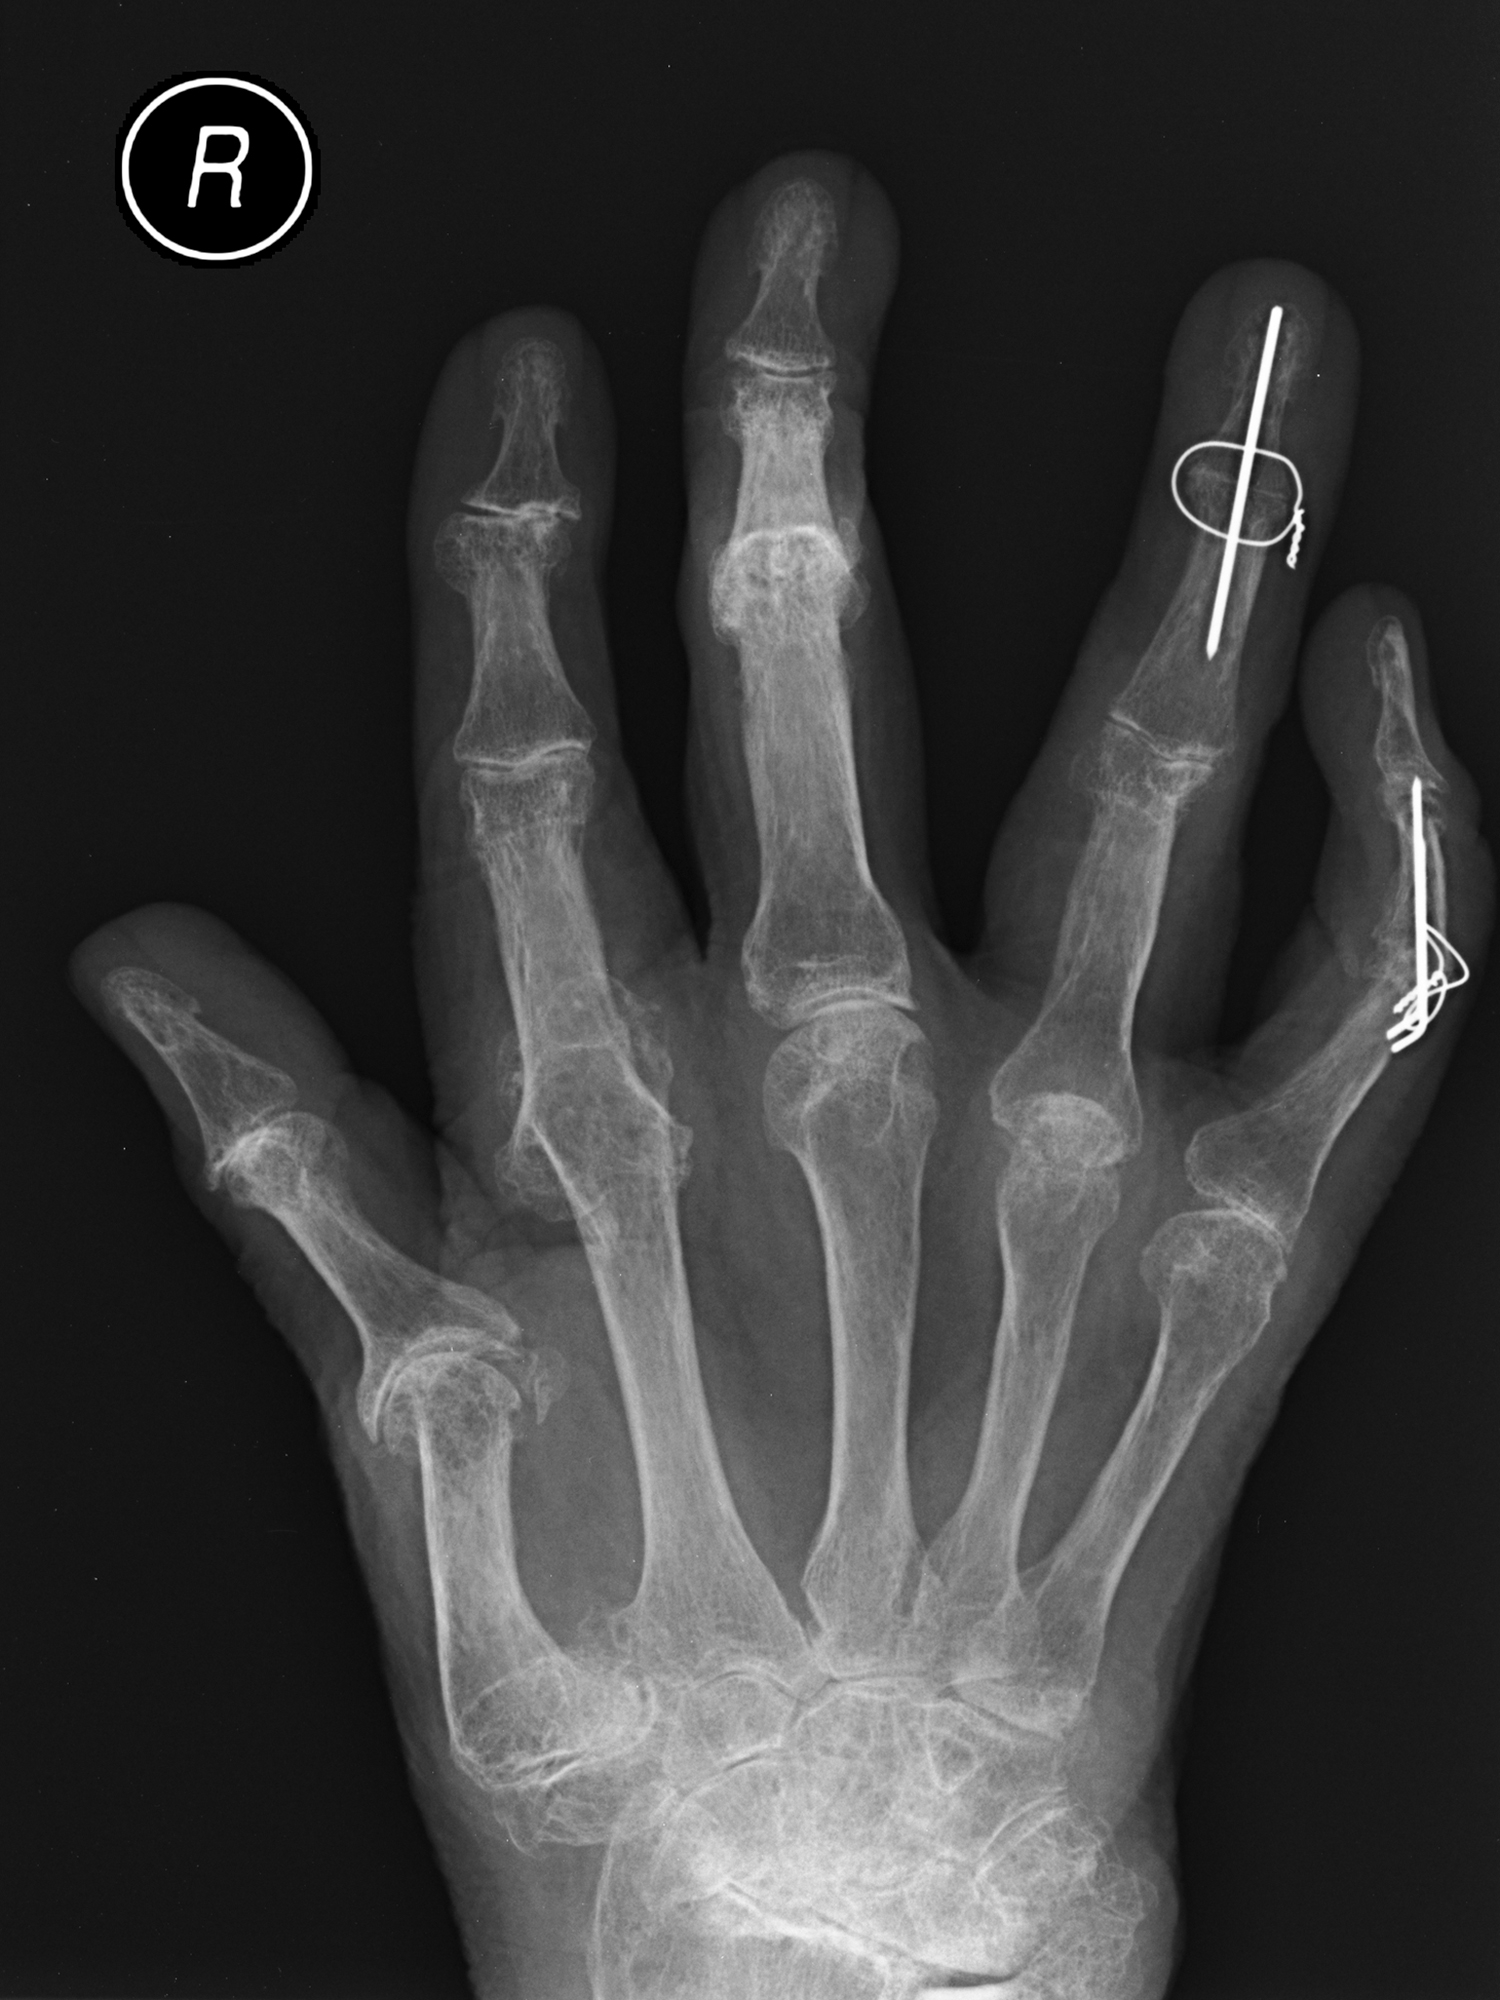

Radiological Features

X-rays provide a record of the permanent damage of RA ( Fig. 59.1 and Box 59.2 ). Changes include: surface erosions, cystic changes, cortical thinning, osteoporosis, and progressive joint narrowing through to frank ankylosis, subluxation, and dislocation. In mutilans arthropathy there is bony destruction, which may progress rapidly.

The Sharp and Larsen scores are the most widely used radiological assessments for RA. Each scores X-rays of the hands, wrists, and feet; higher scores indicate greater bony destruction. The Sharp method scores bony erosions and joint space narrowing separately over 31 areas to give a score from 0 to 448. The Larsen score assesses 20 joints to give a score out of 100. Although the Larsen score is more widely used, the Sharp assessment is more sensitive for detecting changes over time. The Sharp and Larsen assessments have significant correlation with each other and with the extent of joint and cartilage destruction.